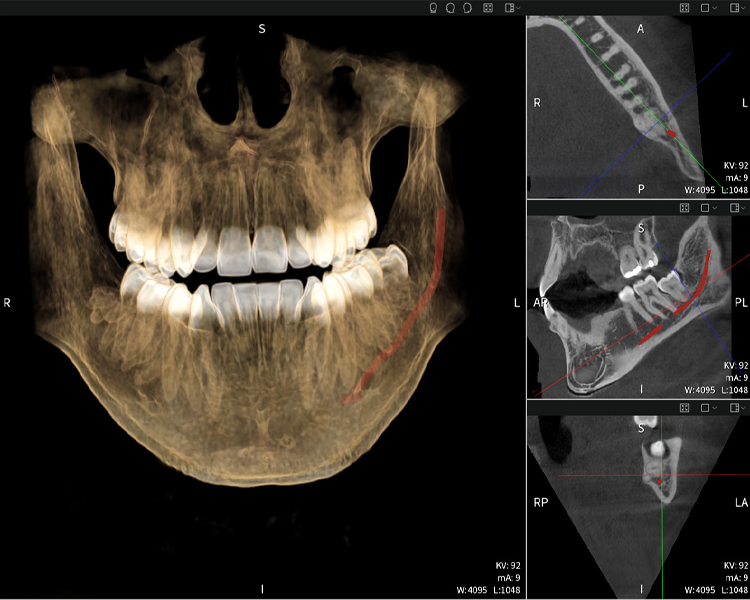

Abbildungen b–d zeigen verschiedene Ansichten einer 3D-Rekonstruktion des Unterkiefers und bieten eine umfassende Übersicht über die Anatomie des Unterkiefers, die Lage der Nerven im Verhältnis zu den Zähnen und ermöglichen die Beurteilung der Zahnsymmetrie und Ausrichtung.

Abbildung d zeigt den bereits vorbehandelte Zahn 48, dessen Krone entfernt wurde und dessen Wurzeln nahe am Nerv belassen wurden, was das hohe Risiko einer Nervenschädigung verdeutlicht.

Abbildung e: Panoramaröntgenaufnahme dient der initialen Beurteilung und zeigt die allgemeine Zahnstellung sowie mögliche pathologische Veränderungen auf. Insbesondere ist auf der rechten Seite (Zahn 48) die Situation nach einer Kronenamputation durch einen externen Behandler ersichtlich. Die beiden stark gekrümmten Wurzeln verbleiben in enger topographischer Beziehung zum Nervus alveolaris inferior im Knochen. Dies deutet auf eine bewusste Entscheidung zur Vermeidung eines erhöhten Risikos einer Nervenläsion während einer vollständigen Extraktion hin und stellt einen klinisch relevanten Befund dar. Zusammenfassend liefern die CBCT-Aufnahmen mit Seethrough Max entscheidende Informationen über die komplexe Anatomie und die kritische Beziehung zwischen den Weisheitszähnen und dem Nervus alveolaris inferior. Diese detaillierte präoperative Diagnostik ist unerlässlich für die sichere und erfolgreiche Durchführung chirurgischer Eingriffe im Unterkieferbereich.